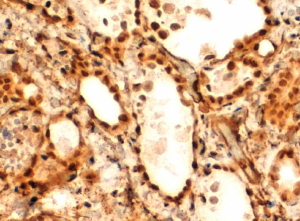

IHC Results In paraffin embedded Human Thyroid Gland shows nuclear staining in thyrocytes. Recommended concentration: 2-4µg/ml. Paraffin embedded Human Testis. Recommended concentration: 5µg/ml. | |